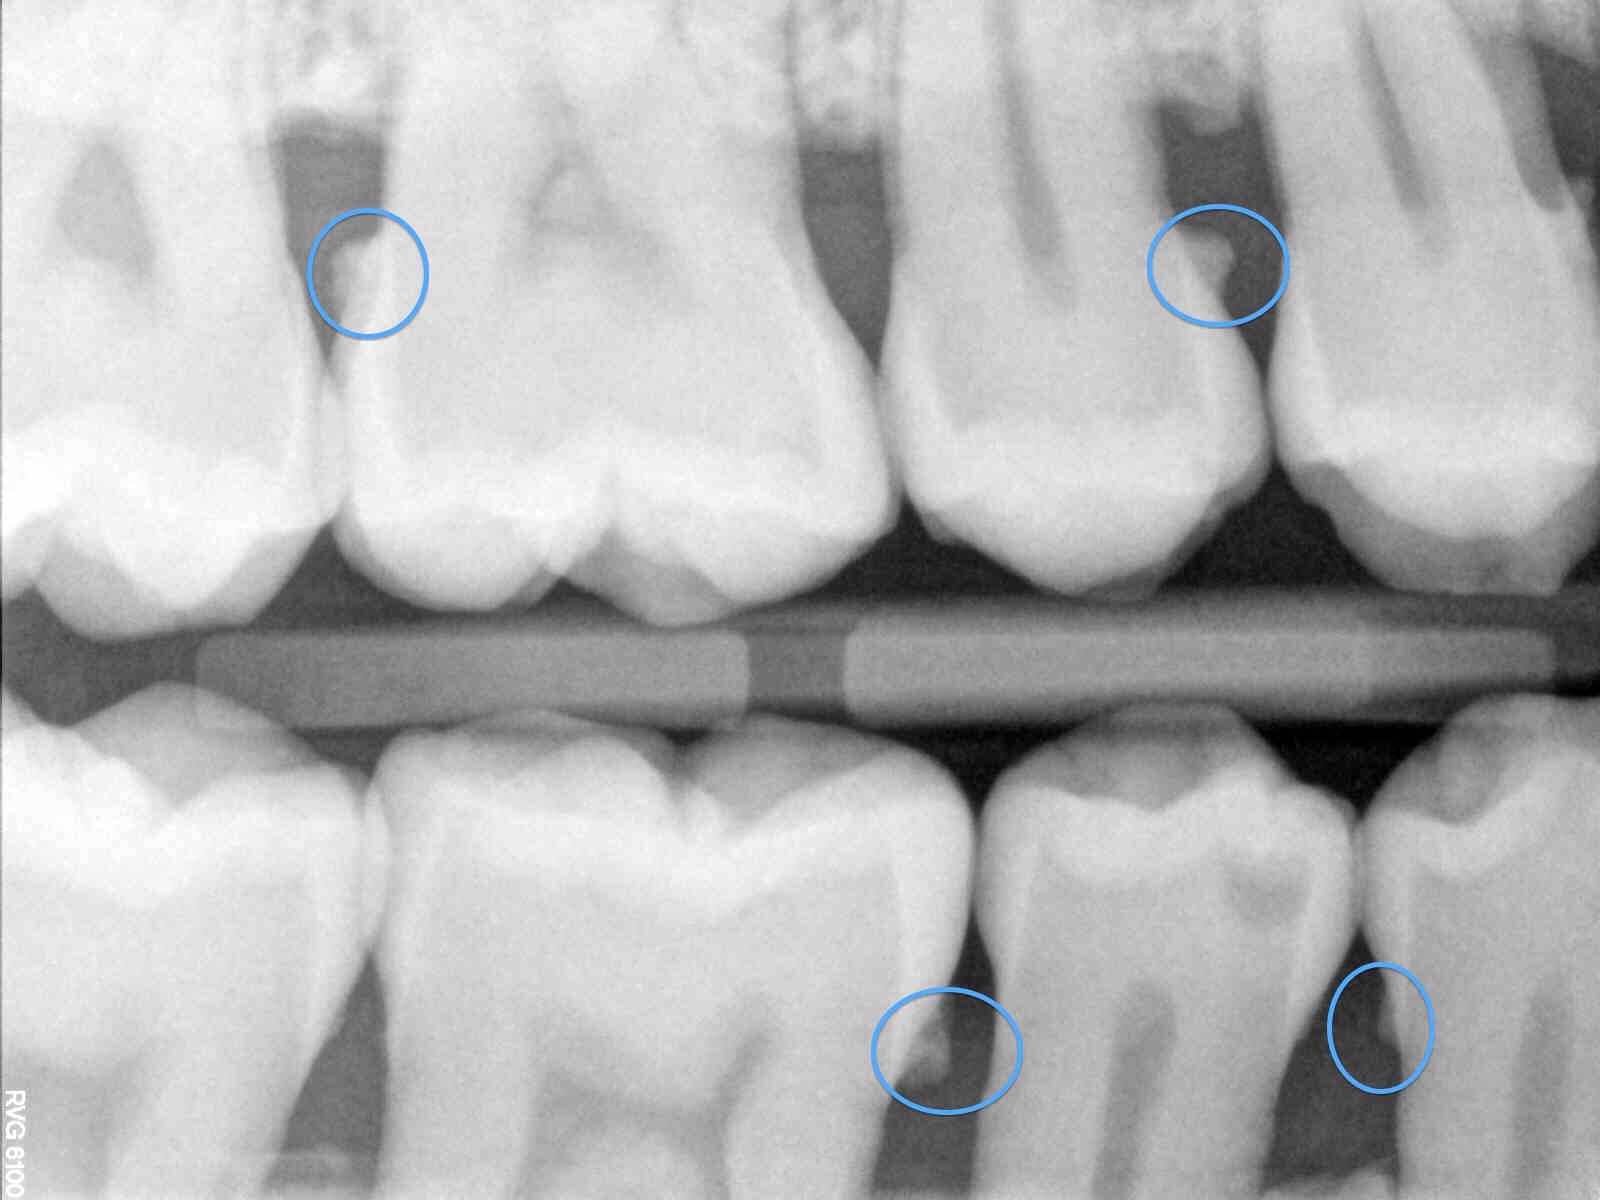

Vôi răng dưới nướu:

→ Vị trí: Dưới viền nướu, bám quanh cổ chân răng

→ Khó phát hiện bằng mắt thường, dễ gây viêm nha chu

Hình ảnh vôi răng dưới nướu trên phim X quang

- Chụp phim X-quang (nếu cần) để kiểm tra vôi răng dưới nướu và tiêu xương ổ răng.